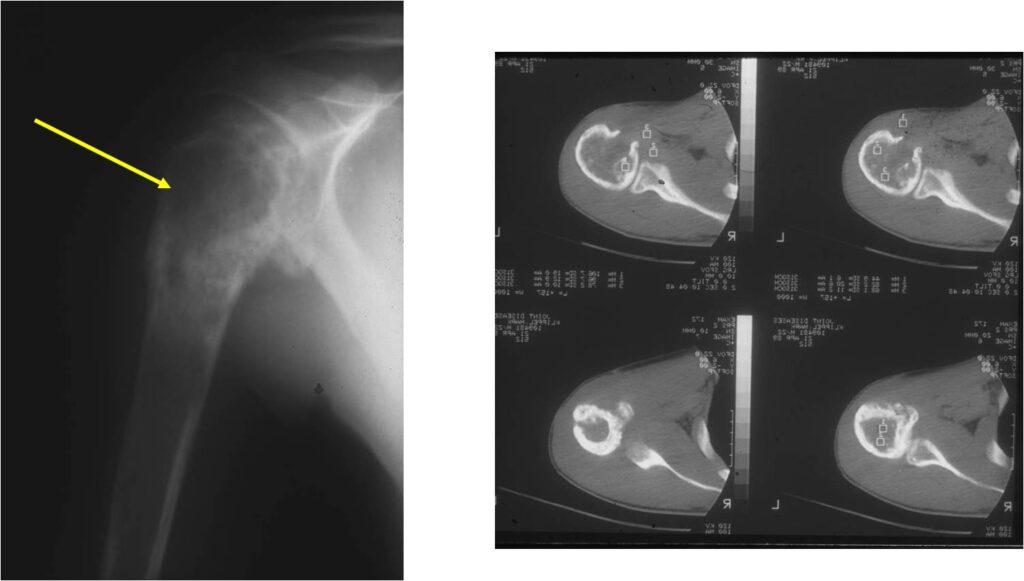

Sites:

- Most commonly arises from diaphysis but can also arise from metadiaphysis and metaphysis;

- Long Bones – Most common

- Femur: Single most common site

- Humerus

Radiographic Presentation

- Permeative or moth eaten bone destruction

- Soft Tissue Mass in 90% of of cases

- Periosteal Reaction in 50% of cases

- Onion Skin (colic pattern of irritation)

- Hair on End (rapid continuous lifting of periosteum)